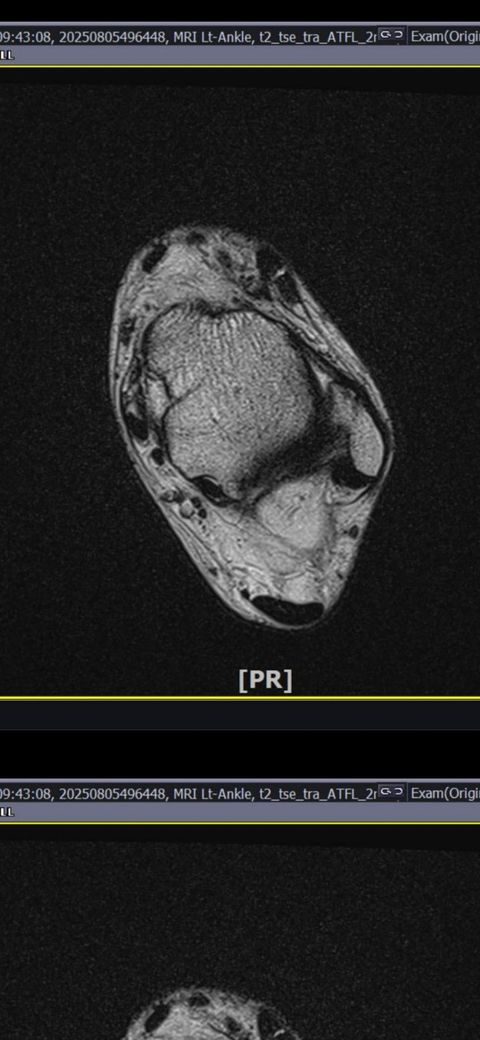

그래도 통증이 남아 8월 5일에 MRI를 촬영했는데, 병원에서는 “인대는 이어져 있고, 이 정도면 재활운동으로 호전될 것”이라는 설명을 들었습니다.

MRI 상 전거비인대와 발목 상태가 정말 회복 단계인지, 아니면 만성으로 넘어가는 건 아닌지 전문가분들의

의견을 듣고 싶습니다.

그리고, 처음 초음파 사진(6월 촬영)과 비교하여

mri 사진(8월 촬영)상 인대가 호전됬는지도

알고 싶습니다.

올려주신 mri를 보면 전거비인대는 연속성이 유지되고 있고 파열이나 큰 손상 흔적은 없어 재활로 회복 가능한 상태로 보입니다 다만 3개월 가까이 활동 시 통증과 미열감이 남아 있는 것은 조직 회복이 아직 완전히 끝나지 않았거나 주변 연부조직 관절 움직임 제한 등으로 인한 과민 반응일 수 있습니다.

초음파와 비교하면 mri 상으로 인대 연속성이 확인되므로 심각한 악화나 재파열은 아닌 것으로 판단됩니다